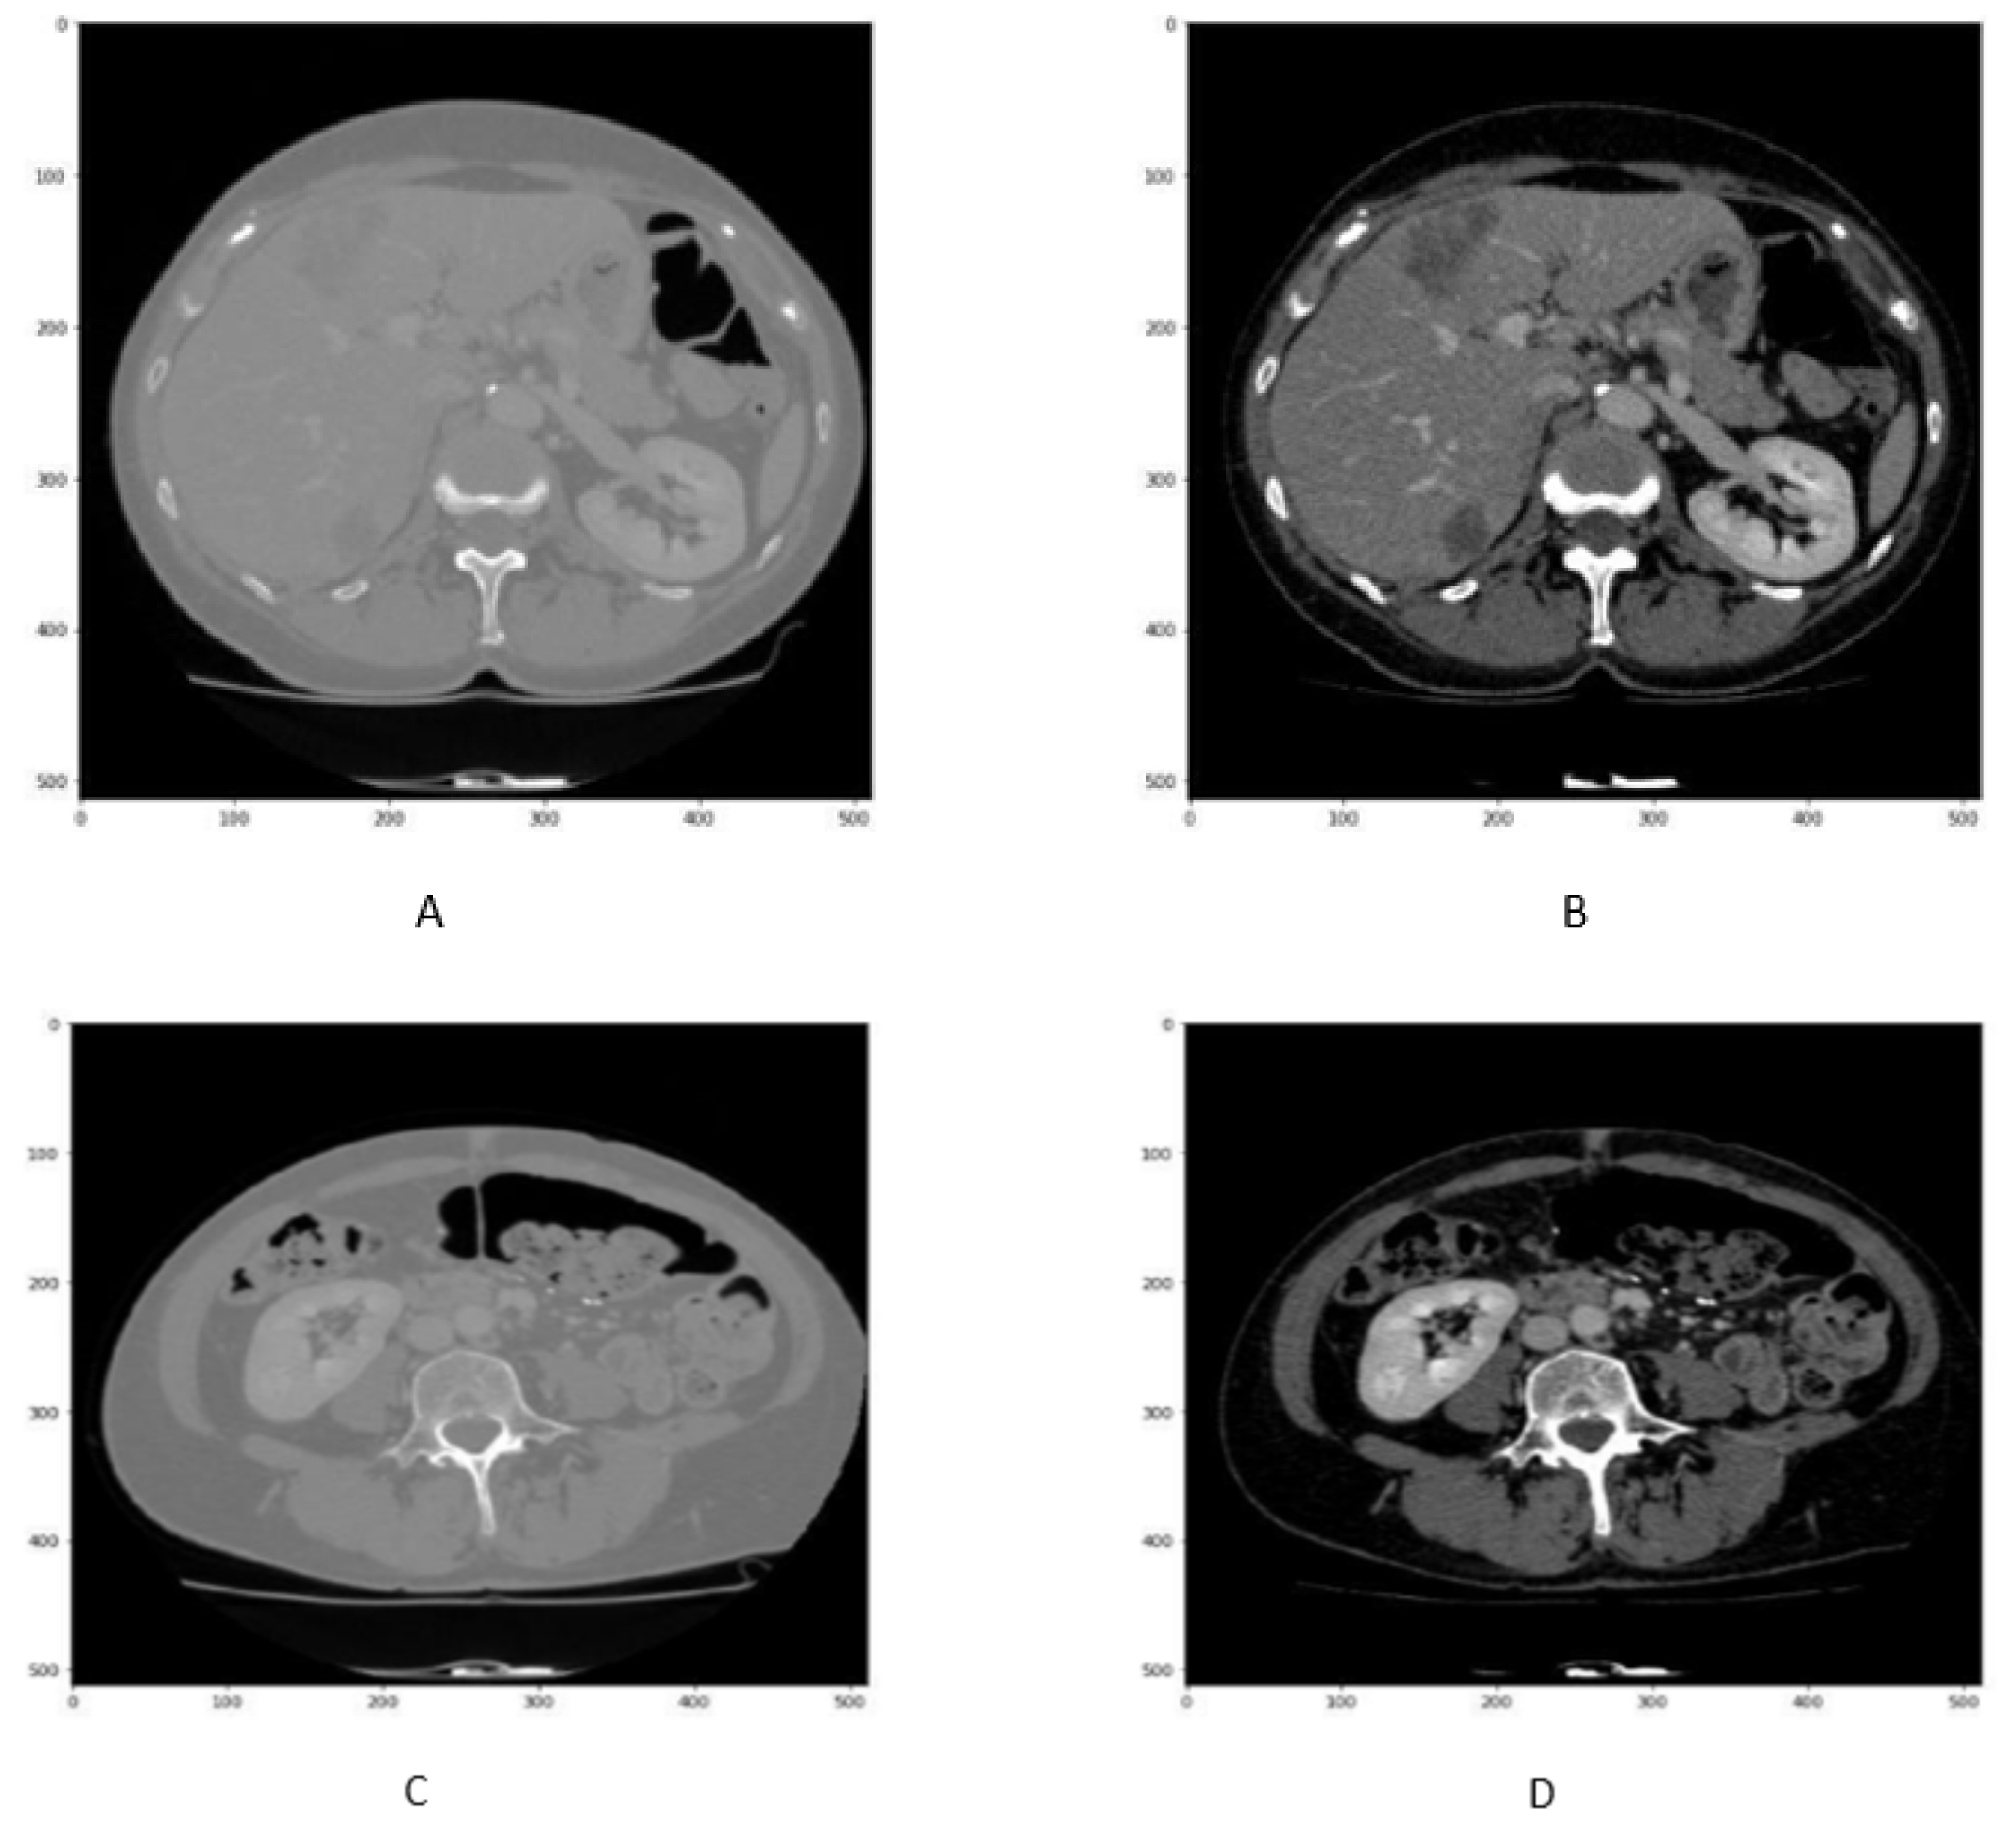

In order to enhance the visualization of the liver, HU windowing is performed at each slice where the HU range of −100 to 400 is selected, as shown in Figure 2. It shows that most organs are occluded in CT image slices without windowing operation, while the image and organs became clearer after HU windowing. Therefore, this HU windowing is performed over all slices before passing them to the next process.

Figure 2.

Figure represents the HU windoing results in (A,B), While Figures (C,D) shows the HU windowing results not having Liver.